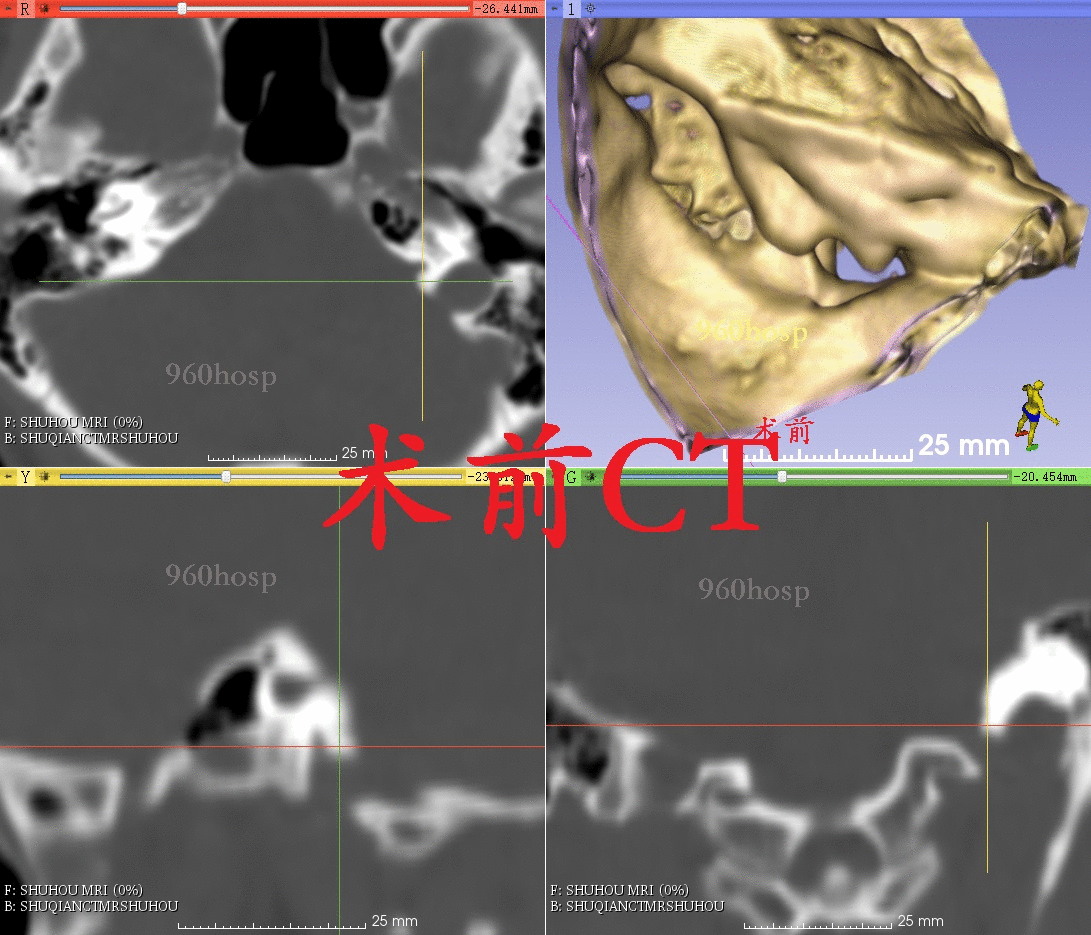

根据患者症状和体征,排除肺部病变,考虑病变定位于左侧颈静脉孔区导致左侧第Ⅹ和第Ⅺ颅神经同时受累。尽管磁共振报告“阴性”,但我们从术前CT和磁共振影像上仔细观察,还是能发现一些蛛丝马迹:CT显示左侧颈静脉孔较对侧略扩大,磁共振增强扫描显示左侧岩下窦汇入颈静脉孔处有不均匀增强信号。

采用3D Slicer对术后复查头颅CT与术前配准,对比显示开颅骨瓣和磨除的颈静脉孔区部分骨质。